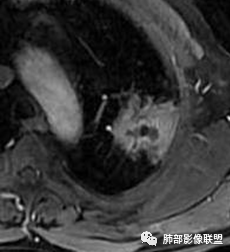

糊墙:肺内病灶不侵犯壁层胸膜或以外,与壁层胸膜相对而言分界清楚。

栽赃:病灶侵入壁层胸膜及胸膜外脂肪间隙、胸壁其他结构等,相对在病灶中央区域,与胸膜分界不清。

南边:看肺内病灶与胸膜分界清,增强后强化不一致,需要综合分析。

这是糊墙。

这就栽赃。都突到外面去了。

看看这个,骨头都侵袭了。